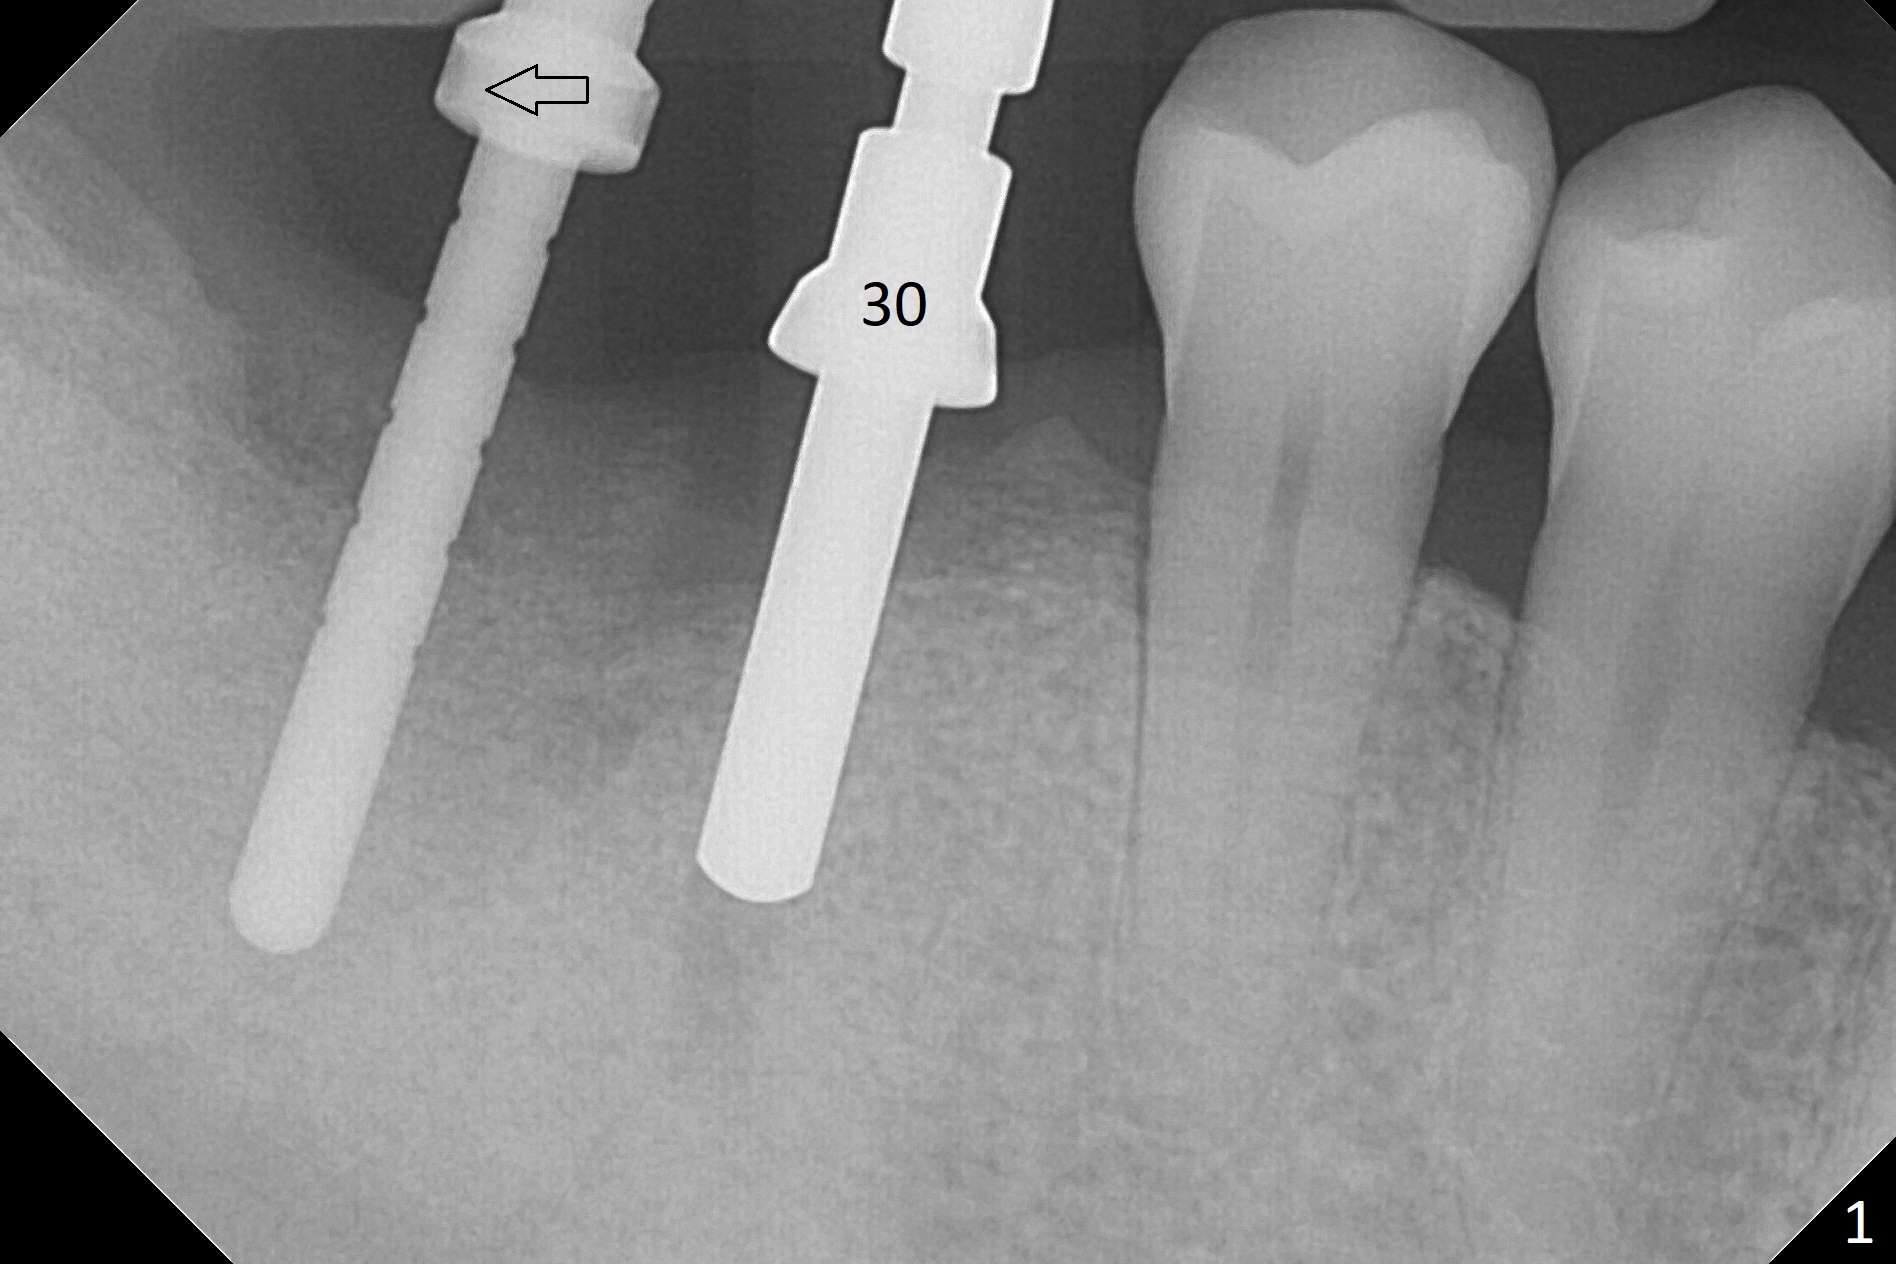

Osteotomy at the sites of #30 and 31 is initiated with Magic Split, followed by Magic Expanders (3.0 and 3.8 mm) at #31.  Initial depth of osteotomy is 13 mm with 2.2 mm drill (Fig.1).  After adjustment of the trajectory at #31 (Fig.1 arrow) and deepening the osteotomy by 2 mm, dummy implants are placed with stability (Fig.2).  Following increase in osteotomy at #31, the larger implant in fact loses stability (Fig.3).  The loose implant is pushed distal (Fig.4 arrow) with placement of autogenous bone mesial (*).  The stable implant at #30 (Fig.3) and its abutment (Fig.4) are used as a post to hold periodontal dressing, which covers the wound at #31 after placement of collagen plug and suturing.  In fact the same technique could be used when socket preservation was performed if an implant were placed at #30 at the same time.  When the periodontal dressing dislodges, the wound at #31 heals uneventfully (Fig.5,6).  The bone graft seems to remain in place 3 months postop (Fig.7).  The implant is uncovered with placement of a 6.8x7 mm healing abutment 4 months postop.  When a cementation abutment is placed and prepped, the buccal margin is much lower than the lingual (Fig.8 taken prior to cementation).  The patient enjoys mastication with the new implant crowns 3.5 months post cementation (Fig.9).